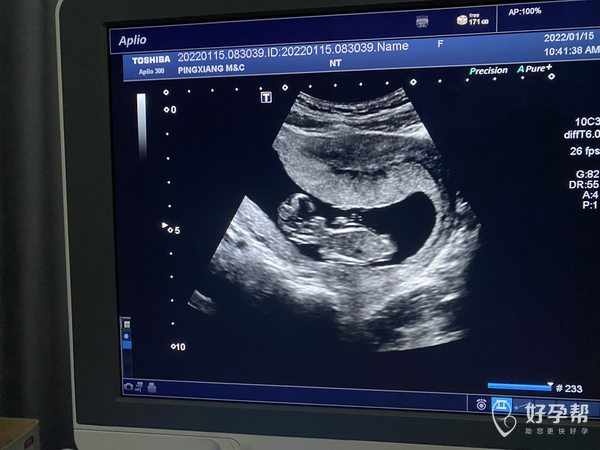

怀孕11周➕1b超是这样的正常吗

很好,一般十四周前NT检查,胎儿发育很好